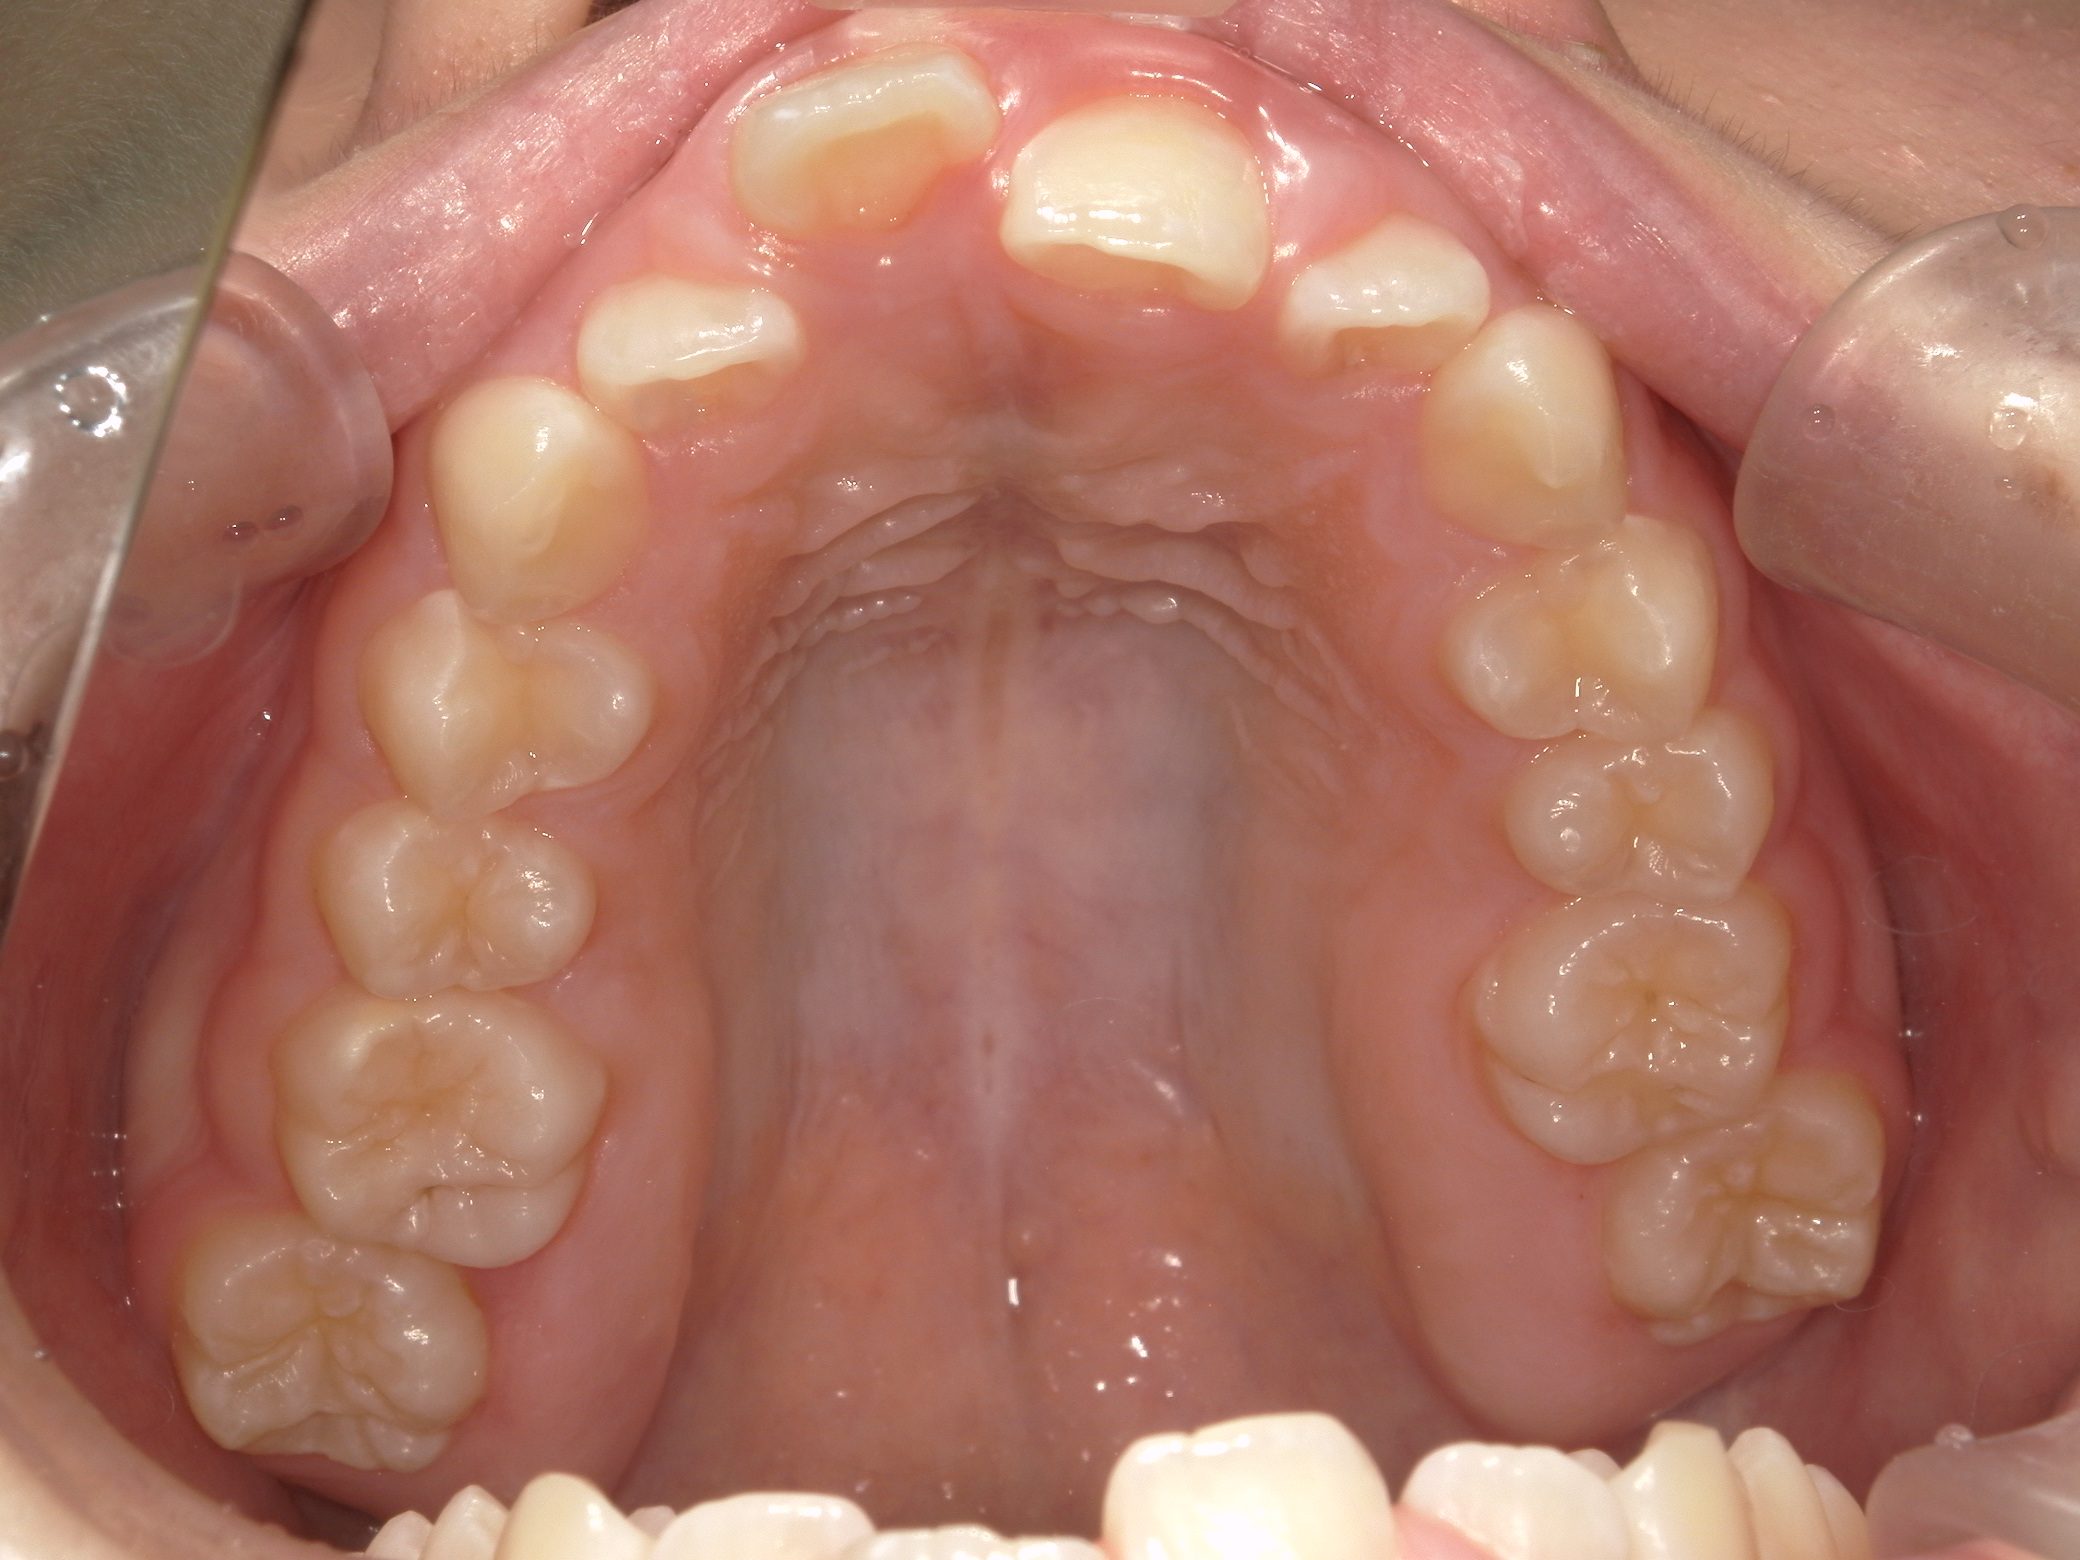

【中学生】インビザライン矯正 上顎前突(出っ歯)を改善

中学生以降

インビザライン フル

出っ歯

過蓋咬合

非抜歯

2期治療のみ

Before

After

治療期間

1.7年

治療開始

14歳歳

種類

インビザライン矯正

使用装置

インビザラインフル ディスキング併用

コメント

しっかり装着してくれて 予定通りに治療が終了しました。